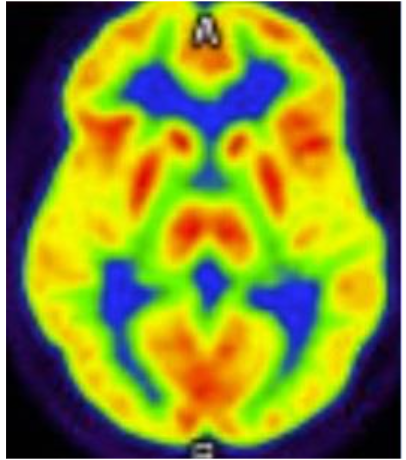

Figure 2 shows a PET-FDG MR Brain axial cross-section performed 14 months later, which re-demonstrates bilateral parietal and occipital hypometabolism, with preserved cingulate island sign, further supporting a diagnosis of dementia with Lewy bodies.

Brain imaging studies, including PET-FDG CT and PET-FDG MR within 14 months of the CT scan, showed hypometabolism in the bilateral parietal and occipital regions with preserved cingulate island sign, supporting the diagnosis of early-onset DLB.

This case demonstrates that DLB can be diagnosed early in life even though the reported average age of diagnosis is 75 years. Computed tomography (CT) imaging of the brain typically does not reveal structural changes, but brain magnetic resonance imaging (MRI) can reveal atrophy in the occipital and parietal lobes and preservation of the temporal lobe volumes. When a brain CT or MRI image is performed with fluorodeoxyglucose positron emission tomography (PET-FDG), it can also reveal occipital and parietal lobe hypometabolism, often with preserved metabolism in the cingulate cortex. Single-photon emission computed tomography (SPECT) scans can also reveal decreased dopamine transporter uptake in the basal ganglia in DLB, but this can also be seen with PD.

Although DLB has a relatively advanced average age of onset, it can occur with an earlier onset especially in inherited forms. Although multiple genetic mutations have been reported with early-onset DLB, this case reveals a relationship between early-onset DLB and a mutation in the PRKN gene. While DLB and PD are both synucleinopathies, mutations in the PRKN gene have heretofore reported as common causes for early-onset PD, but not DLB. This patient’s clinical symptoms and neuroimaging, including PET-FDG Brain imaging, support the diagnosis of DLB instead of PD or AD, indicating a new association with PRKN gene mutations and development of early-onset DLB. This case demonstrates the importance of early testing for dementia for patients under the age of 50 years who show historical and clinical signs of cognitive decline and behavioral changes, especially if they have a family history of dementia, since this can lead to early diagnosis and treatment.